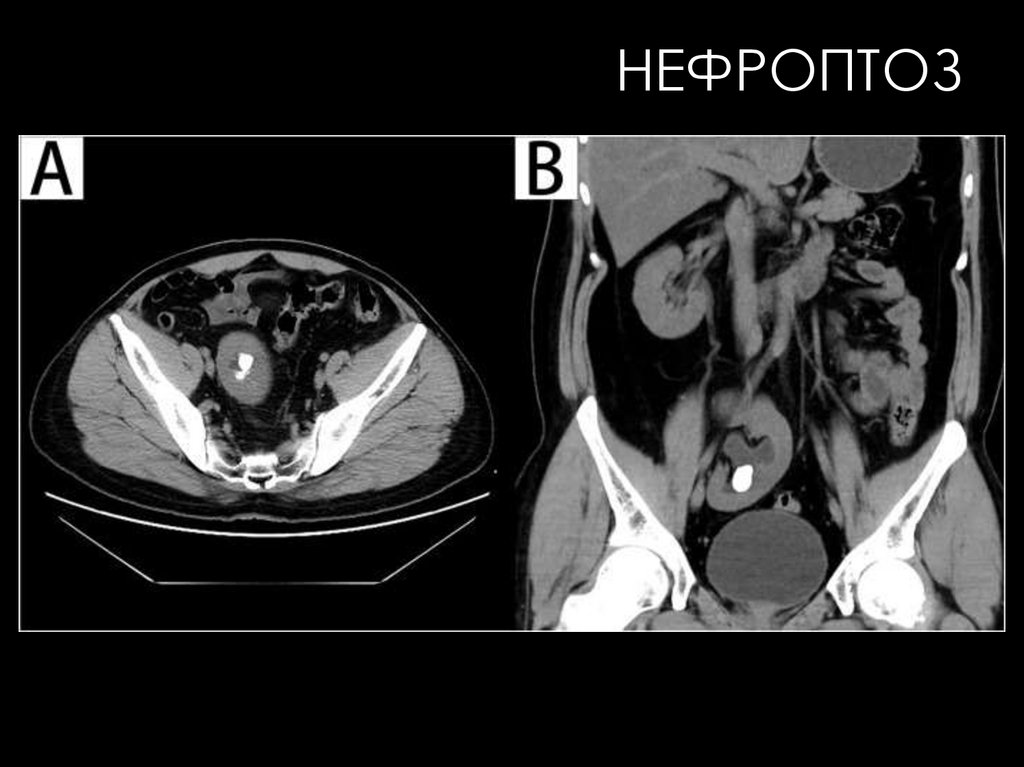

НЕФРОПТОЗ

позволяют не только получить представление о структурных